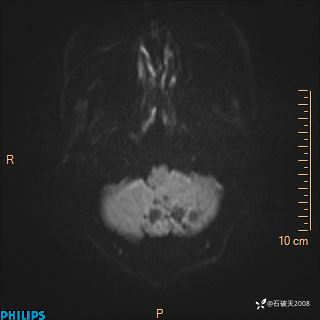

DWI